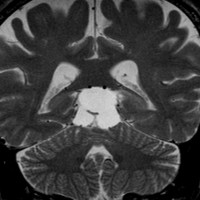

放射線化学療法後の画像です。腫瘍境界は不明瞭(左)で,腫瘍内出血(中央)して,左の視床に浸潤しています。かなりリスクは高いのですが,これを開頭手術で全摘出しました(右),この時点で完全寛解 CR です。この後にさらに化学療法と幹細胞移植(PBSCT,大量化学療法)が加えられました。